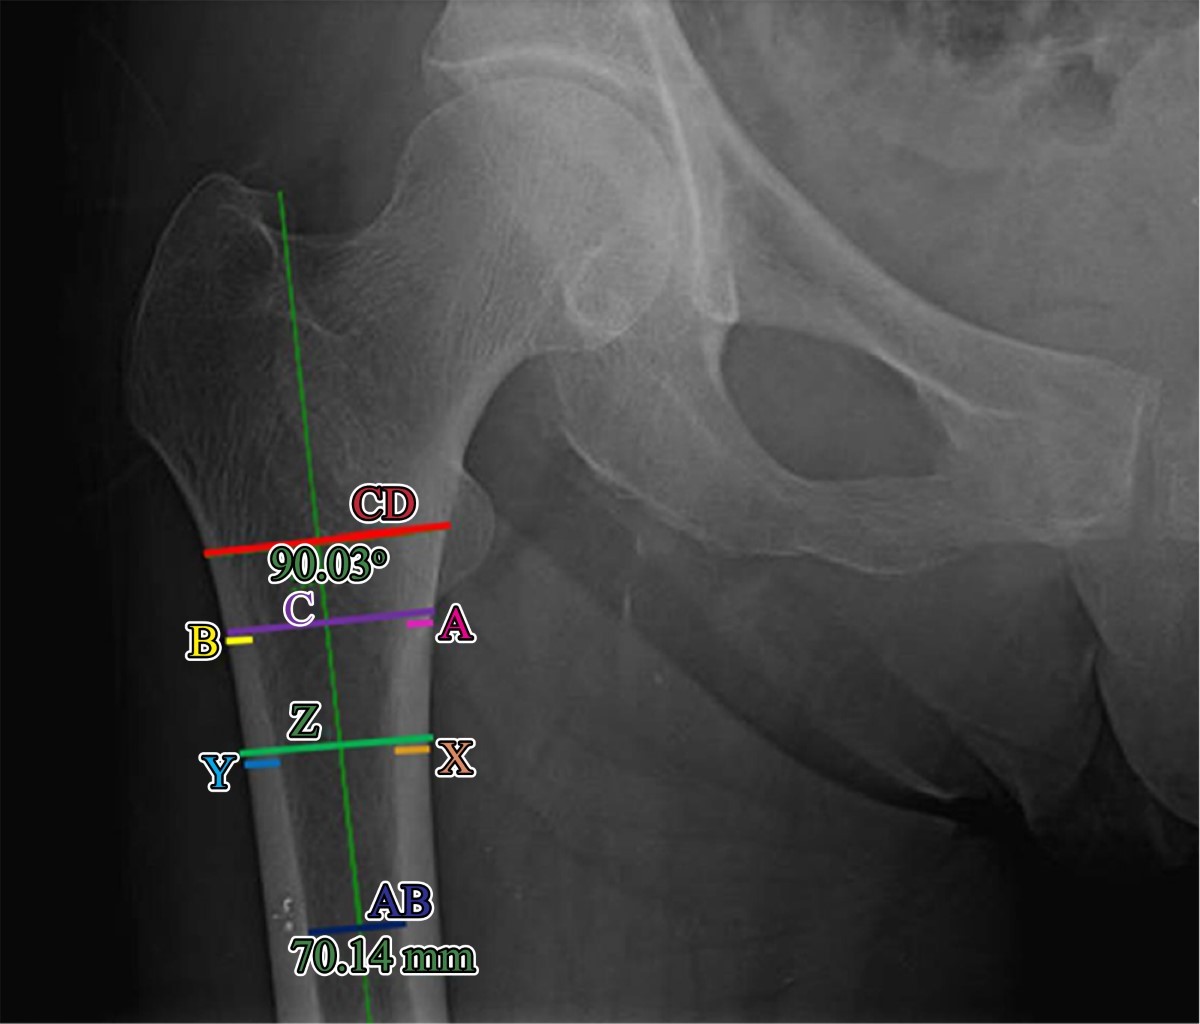

Mediciones radiográficas: se midieron los diámetros CD y AB requeridas para el cálculo del índice morfológico cortical (IMC: CD/AB); el diámetro C y las corticales A y B fueron empleadas para calcular el índice corticometafisario (ICM: A+B/C); y el diámetro Z y las corticales X y Y se usaron para el cálculo del índice corticodiafisario (ICD: X+Y/Z).

Estandarización de evaluadores: los tres evaluadores participantes fueron estandarizados en la técnica de medición radiográfica para reducir errores en el cálculo de los índices como se ilustra en la Figura 1 y se detalla a continuación:

Índices morfológico cortical (IMC): a) trazo de una línea longitudinal en el centro de la cavidad medular correspondiente al eje anatómico femoral, b) identificación del punto más alto del trocánter menor, c) trazo de línea perpendicular (90°) a la porción externa de la cortical lateral, d) al nivel de la línea trazada en el paso anterior se traza una línea entre ambas porciones externas de la cortical medial y lateral para medir el diámetro CD, e) se traza una línea perpendicular hacia la cortical medial distales del centro del diámetro CD y f) sobre esa última línea se mide el ancho del canal endomedular a 70 mm para obtener el diámetro AB.

Índice corticometafisiario (ICM): a) trazo de una línea longitudinal en el centro de la cavidad medular correspondiente al eje anatómico femoral, b) identificación de la base del trocánter menor, c) trazo de línea perpendicular (90°) al eje femoral y medición del diámetro C comprendida entre las corticales externas de la cortical medial y lateral, d) medición de la cortical medial A y lateral B al nivel de la base del trocánter menor.

Índice corticodiafisiario (ICD): se siguen los mismos pasos que en el ICM, pero las mediciones se realizan a 20 mm distales a la base del trocánter menor para obtener el diámetro Z entre las corticales externas de la cortical medial y lateral y las mediciones de la cortical medial X y lateral Y.